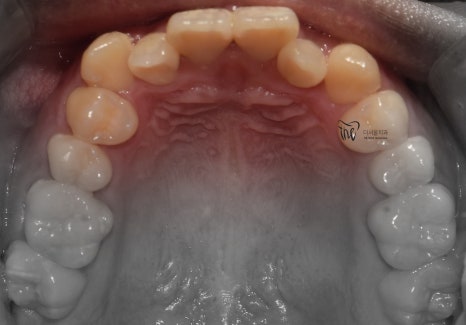

『11개월 소요, 치료 결과 안내』

따라서, 11개월 이라는 기간이 소요되어서

치료 종료가 되었습니다.

치열이 많이 가지런하게 펴진 것을 볼 수 있고,